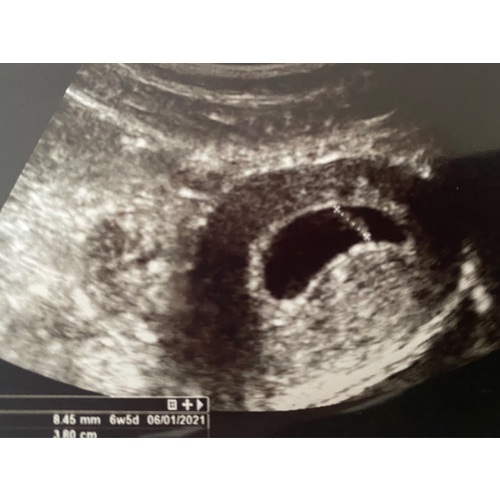

Ben ik het niet helemaal eens. Ik was 6 + 5 dagen, en er was overduidelijk een placenta met een vruchtje te zien, met een kloppend hartje. Die van mij was ook uitwendig. Neemt niet weg dat de verloskundige misschien niet kundig genoeg was, maar dat je uitwendig niks kan zien is niet waar.

Ja wel knullig dat ze dat zo gedaan hebben. Waar ik zit allemaal heel kundig, maar de meeste echo's die worden gedaan zijn bij ons in het echocentrum. Uitwendig zag ik wel e baarmoeder en vruchtzakje met 6 weken maar het vruchtje niet. Toen meteen inwendig en was het meteen goed te zien. Ik duim voor je dat er de volgende keer wel iets te zien is, maar ik zou toch zeker vragen voor een inwendige echo want dan is het zeker beter te zien.